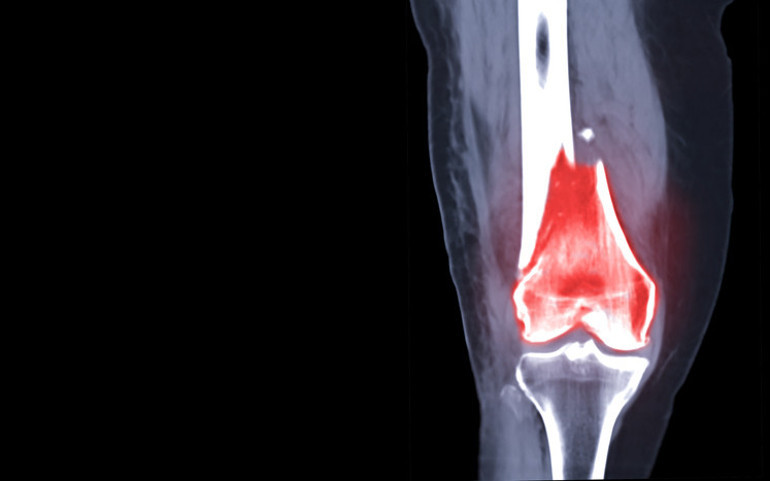

Dev hücreli tümörler kelimenin tam anlamıyla milyonda bir görülen bir hastalıktır. Amerikan Ortopedik Cerrahlar Akademisi'ne göre, sadece 1 milyon kişiden birinde görülür. Bu tümörler kanser olmamalarına rağmen çok agresiftirler ve tedavi edilmezlerse büyümeye devam ederler. En sık bacaklarda, diz eklemi yakınında görülürler ve çevredeki kemikleri de tahrip edebilirler.

Ashley, nihayet 13 Ocak'ta ağrıları başladıktan iki ay sonra tümörü çıkarmak için iki saatlik bir ameliyat geçirdi. Cerrah ayrıca kemiğinde tümörün neden olduğu çatlakları doldurmak için kemik çimentosu kullandı.

Kemik çimentosu, akrilik yani polimetilmetakrilat denilen maddeden üretiliyor ve yaklaşık 60 yıldır ortopedi alanında kullanılıyor. Protez ameliyatlarında, kemik tümörlerinin tedavisinde, bazı kırıklarda ve bel kemiği çökmelerinde kullanılan bu madde 15 dakika gibi kısa bir sürede donar.

Ortopedi ve Travmatoloji Uzmanı Dr. Tarık Elma, kemiklerde görülen dev hücreli tümörlerin aslında kötü huylu kanserlerden olmadığını fakat iyi huylu tümörler olmasına rağmen bulunduğu kemikte aynen bir elma kurdunun elmayı içten kemirmesi gibi bulunduğu kemiği içten çürütmeye ve inceletmeye başladığını söyledi.

Elma, burada erken tanının çok önemli olduğunu, çünkü bazen hastalanan kemiklerdeki bu ağrılarını önemsemezse bu tümörün kemiği içten içe yiyerek zayıflatacağını ve kemiğin içini boşaltacağını, içi boşalan kemiğin de çok ufak bir darbede veya ani bir hareket sonucunda ciddi şekilde kırılabileceğinin altını çizdi. Erken tanı konması durumunda ise tedavisinin oldukça basit olduğunu ve yapılacak cerrahi müdahaleler ile tümörün temizlenerek kemiğin tekrar güçlendirilebileceğini sözlerine ekledi.